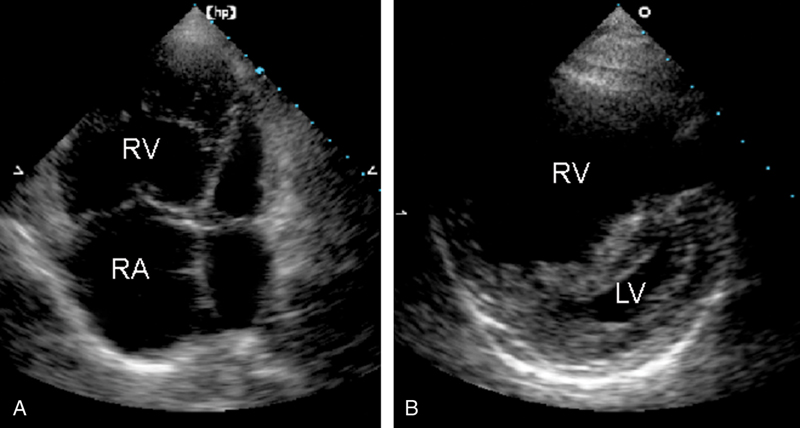

فحوصات تشخيصية لبعض امراض القلب والشرايين التاجية